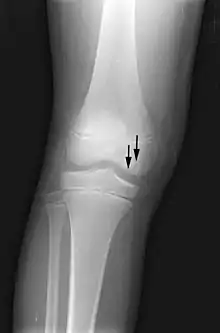

Front X-ray of right knee of an adolescent (epiphyseal plates are open): arrows point to avascular necrosis and developing osteochondritis dissecans in the outer medial condyle of femur

In the early stages, bone scintigraphy and MRI are the preferred diagnostic tools.[18][19]

X-ray images of avascular necrosis in the early stages usually appear normal. In later stages it appears relatively more radio-opaque due to the nearby living bone becoming resorbed secondary to reactive hyperemia.[2] The necrotic bone itself does not show increased radiographic opacity, as dead bone cannot undergo bone resorption which is carried out by living osteoclasts.[2] Late radiographic signs also include a radiolucency area following the collapse of subchondral bone (crescent sign) and ringed regions of radiodensity resulting from saponification and calcification of marrow fat following medullary infarcts.